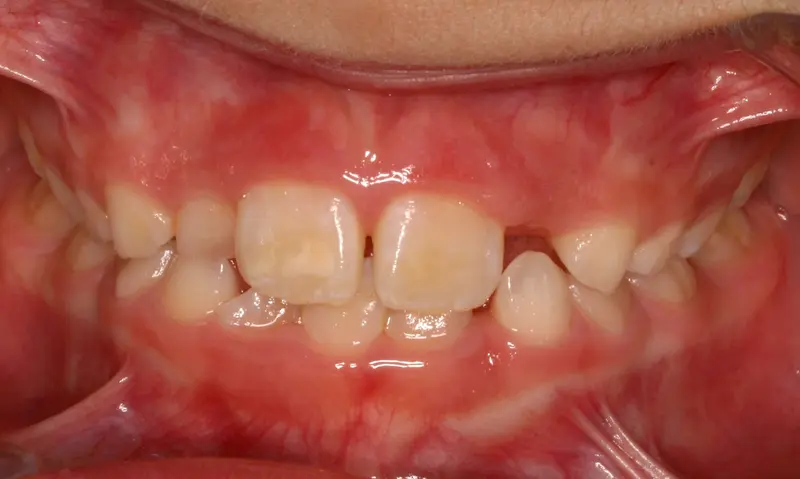

Phase 1 Early Intervention 12 Months

The Expansion Phase

The Diagnosis

Severe crowding with blocked-out permanent teeth. The jaw size was insufficient to accommodate the erupting adult teeth, leading to significant rotation and displacement.

The Engineering

By intervening early, we utilized rapid palatal expansion to develop the arch width. This created the necessary space for the permanent teeth to erupt naturally, avoiding the need for future extractions.

Instrument: Growth Guidance

After treatment: The Expansion Phase

After

Before treatment: The Expansion Phase

Before